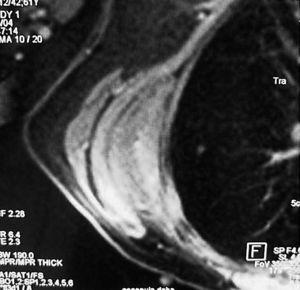

Mujer de 40 años, fumadora, que consultó por un bulto no doloroso en región escapular de un año de evolución que aumentaba de tamaño, alcanzando 7 cm de diámetro. La RMN mostró una tumoración en músculo serrato mayor derecho, en contacto con la pared costal debajo del músculo dorsal ancho que se continúa hasta el músculo subescapular (fig. 1). Era compatible con tumor de alta agresividad, descartandose fibrohistiocitoma u otro sarcoma de partes blandas. Se realizó una biopsia incisional, en anatomía patológica con el resultado de ED. Se practicó una resección marginal, encontrando el tumor ampliamente adherido a la pared torácica y escápula. Se confirmó el diagnóstico de ED tras el análisis de la pieza.

Figura 1. Corte coronal de resonancia magnética nuclear (RMN) en el que se observa un elastofibroma dorsi; se aprecia la tumoración en contacto con la pared torácica bajo el músculo dorsal ancho.